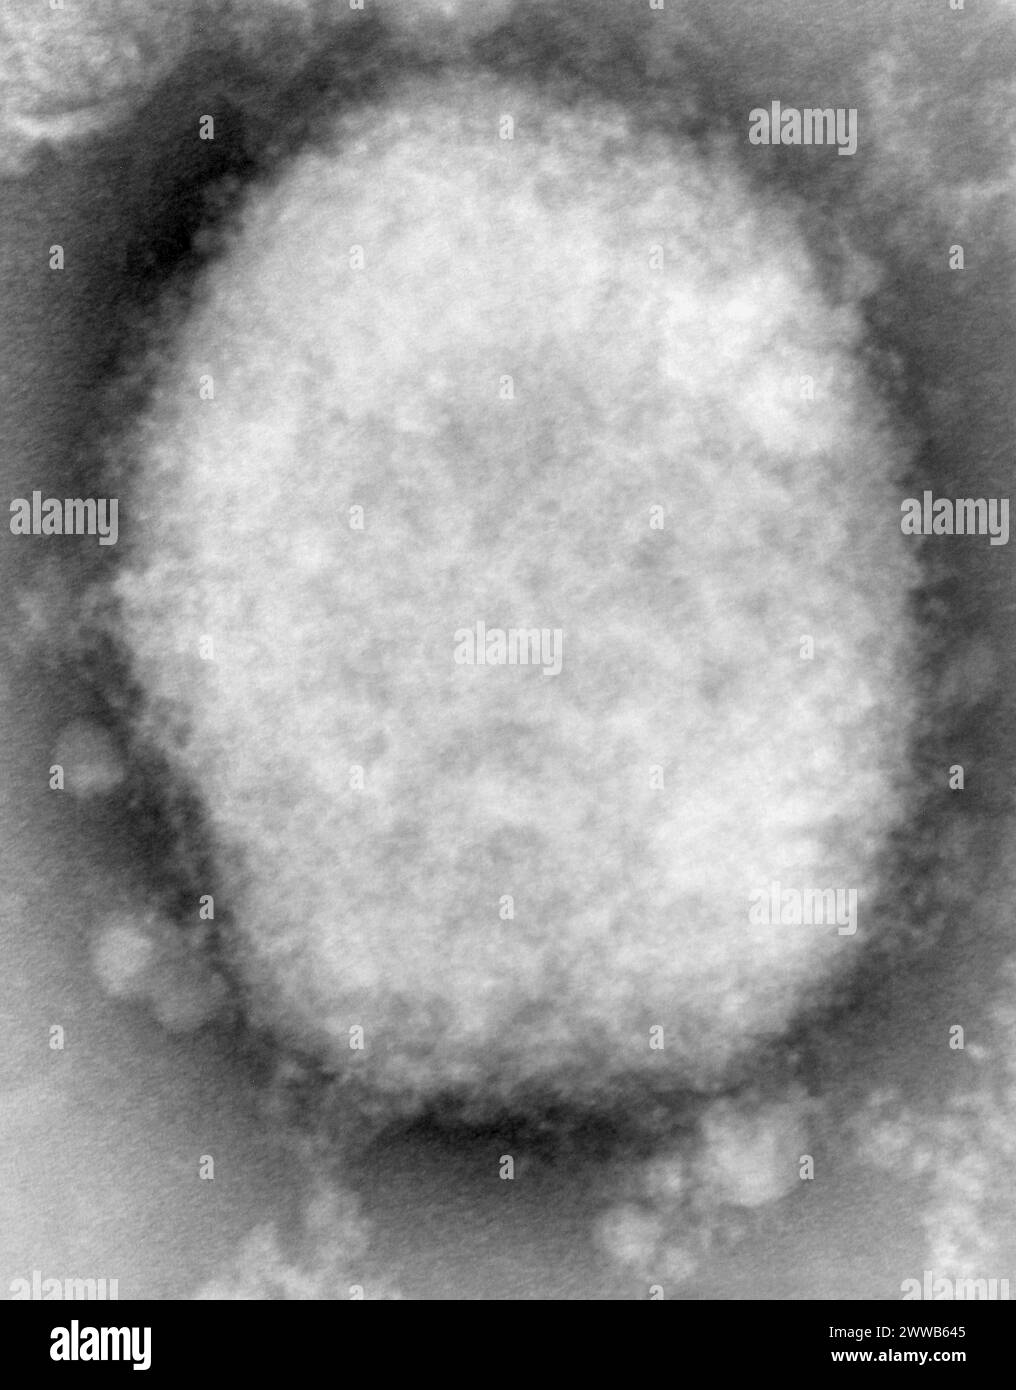

RM2WWB645–Questa immagine altamente ingrandita micrografica elettronica a trasmissione di punti negativi (TEM) rivela un virus del vaiolo monkeyico di tipo M, o gelso.